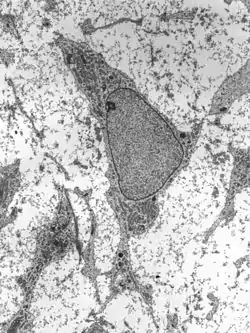

![]() نمای میکروسکوپ الکترونی عبوری از سلولهای بنیادی مزانشیمی که نمایانگر ویژگی فراساختاری معمول آن است. | |